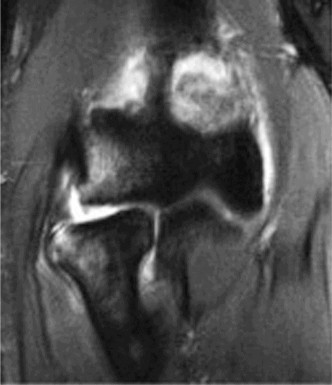

The correct answer is (B). An MRI showing a rotator cuff tear is considered diagnostic of a rotator cuff tear because of its high sensitivity, specificity, and accuracy. It has superb soft tissue imaging abilities (see Fig. 2–5). However, it should be noted that while MRI usually can differentiate between partial- and full-thickness rotator cuff tears, this varies with the power and accuracy of the MRI facility. This is also true with the ability of MRI to differentiate between partial-thickness rotator cuff tears and subacromial bursitis. An arthroscopy is needed for definitive differentiation of these pathologies.

Figure 2–5_Coronal oblique view MRI slice of a left shoulder. (Reproduced with permission from Smithius R and van de Woude HJ. Shoulder MR Anatomy: Normal Anatomy, Variants, and Checklist. _Radiology Assistant. April 2, 2012.)

MRI remains the most popular imaging modality for diagnosing rotator cuff tears. Normal rotator cuff tendon appears dark on both T1 and T2 sequences. Tears may be noted as being full-thickness, articular-sided, bursal-sided, or intrasubstance. They are visualized as a disruption in the regular contour of the tendon and increased signal intensity on T2 sequences. Occasionally, an MR arthrogram may provide additional information regarding a cuff tear, although this is not routinely ordered.

The correct answer is (D). T2 sequence causes most soft tissues, including muscle and tendon, to appear dark and inflammation, such as at the site of a tear, to appear bright. This means that if there is a rotator cuff tear, there will be a bright spot along the course of the dark rotator cuff tendon. This is easiest to pick out in the coronal plane because the tendon runs in this plane, allowing one to view the entire supraspinatus tendon and tear in one cut.